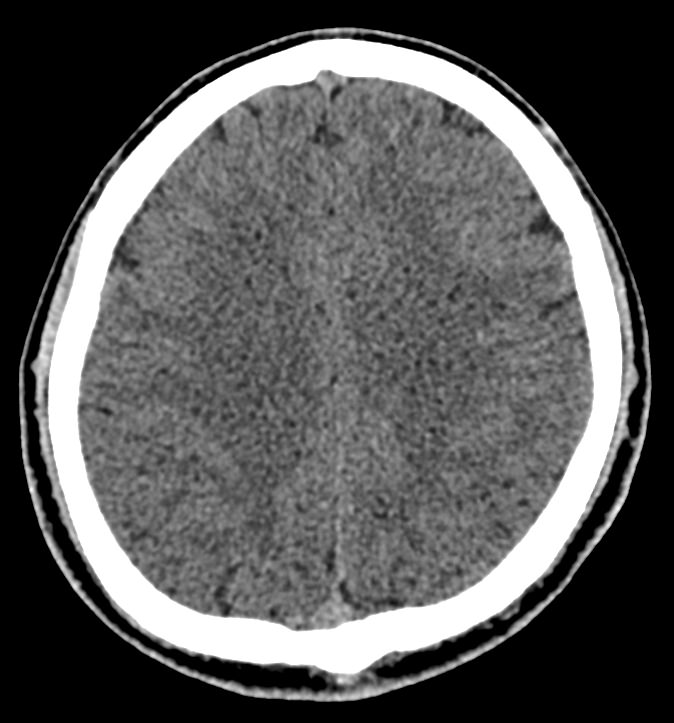

Мультиспиральная компьютерная томография головного мозга относится к лучевым методам диагностики заболеваний центральной нервной системы.

Методика построена на использовании проникающей способности рентгеновских лучей, которые в различной степени поглощаются органами и тканями (степень поглощения зависит от их плотности), благодаря чему можно получить подробные изображения внутренних органов. Во время исследования трубка томографа вращается вокруг пациента и производит снимки поперечного сечения, что позволяет детально визуализировать кости черепа и все структуры головного мозга.

Наши медицинские центры оснащены новейшими мультиспиральными компьютерными томографами экспертного уровня TOSHIBA AQUILION в различных модификациях. Аппараты снабжены увеличенным количеством сверхчувствительных детекторов, что позволяет при сканировании выполнять от 64 до 128 срезов поперечного сечения с минимальной толщиной среза от 0,5 мм. В результате получаются изображения исследуемой зоны в мельчайших подробностях, которые затем с помощью инновационных цифровых приложений преобразуются в трехмерные пространственные модели головного мозга для более точной диагностики.

Нативное сканирование подходит для диагностики дистрофических изменений головного мозга, определение острого нарушения мозгового кровообращения, как ишемического, так и геморрагического характера, а также отслеживание последствий подобных состояний при прохождении реабилитации.

Что можно выявить на КТ головного мозга?

- отек мозга;

- кисты, кистозно-атрофические изменения

- смещение внутренних структур головного мозга.